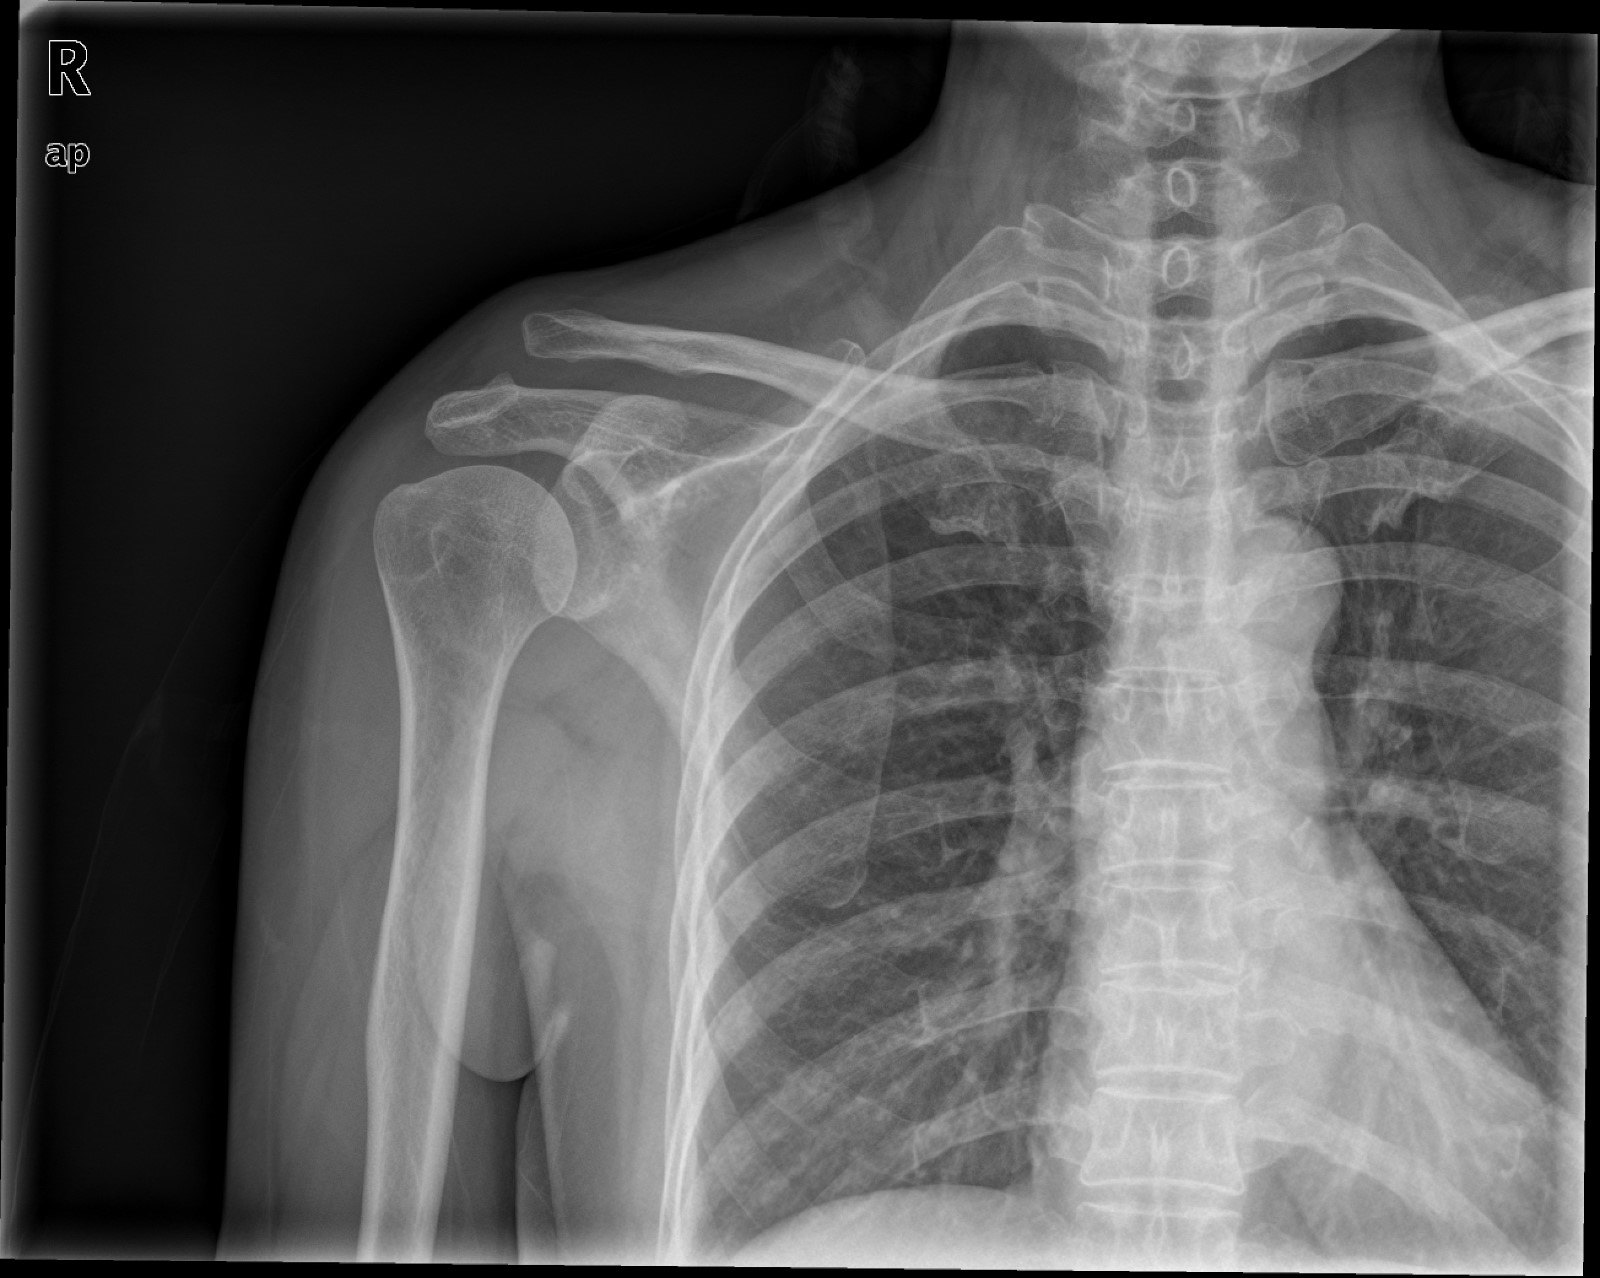

鎖骨骨折のまとめ 鎖骨の解剖 治療 手術適応と治療期間 鎖骨骨折にも色々あります 研修医 救急医のための整形外科 外傷 スポーツ医学マニュアル

「1鎖骨近位端骨折」はほとんど見たことが無いというくらい珍しい骨折ですので、ここでは「 2鎖骨骨幹部骨折 」と「 3鎖骨遠位端骨折 」についてお話しします。 どの骨折についてもたいていは3か月程度の治療期間かかりますが、手術をするかしないかでも治療期間が変わるのが普通です。・鎖骨のどこを骨折した? ・鎖骨骨折かどうかどうやって分かった? ・治療方法と治療期間は? ・痛みはいつまで続く? ・装具固定中はどんなリハビリをすれば良い? ・骨がくっついたらどんなリハビリをすれば良い? ・骨折どんな服を着れば良い?骨折は怪我の中でも、完治するまでに長い期間を要するもので状態によっては入院や手術が必要になります。骨がくっつくまでにどれくらいの期間がかかるのでしょうか? 部位別治療期間 それぞれの部位別の治療期間をみてみましょう。 ・中手指骨折 2週間 ・肋骨骨折 3週間 ・鎖骨骨折 4

・鎖骨のどこを骨折した? ・鎖骨骨折かどうかどうやって分かった? ・治療方法と治療期間は? ・痛みはいつまで続く? ・装具固定中はどんなリハビリをすれば良い? ・骨がくっついたらどんなリハビリをすれば良い? ・骨折どんな服を着れば良い?鎖骨骨折をしたら知っておいて欲しいこと 鎖骨バンドは二枚以上必要 鎖骨を骨折して、病院に行くと 鎖骨バンド と呼ばれるものを処方されます。 手術をするほどの怪我の場合はされないことがあります。鎖骨骨折の治療 鎖骨骨折の治療法は保存療法と手術療法に分けられます。 保存療法 鎖骨骨折は比較的予後が良好であるため、多くは保存療法が選択されます。 骨の転移が大きくなければ整復をして固定する方法が一般的に用いられます。